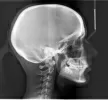

Мой ортодонт посоветовала удалить все 4 зуба мудрости, так как у меня скученность и будет недостаточно места для устранения кривизны зубов. Но на приеме у стоматолога-хирурга мне сказали, что правый нижний зуб расположен очень близко к нижнечелюстному нерву и удаление может повлечь за собой много последствий, вплоть до парестезии подбородка или щеки на всю жизнь. Я очень расстроилась по этому поводу, так как давно мечтала иметь красивую улыбку.

Действительно, правый нижний восьмой зуб находится в нижнечелюстном канале. Удаление данного зуба может повлечь нарушение целостности нижнечелюстного канала. Но если не удалять, то восьмой зуб может стать причиной повреждения седьмого зуба.